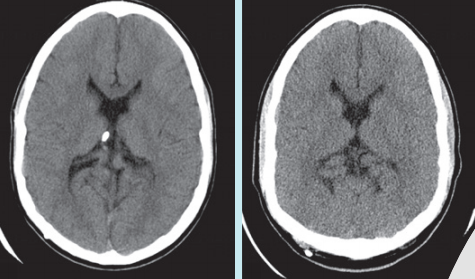

영상의학과에선컴퓨터단층촬영(CT)이 암이나 치아 이상 등 다양한 질병을 진단하기 위해 쓰이는 유용한 기술이다. 짧은 시간 동안 많은 양의 방사선에 노출된다는 점 때문에 주의할 필요가 있다. 다량의 방사선에 노출되면 세포 속 DNA에 이상이 생길 수 있다. 문제는 방사선량을 줄이면 영상의 화질이 나빠진다는 점이다.

● 딥러닝으로 CT 촬영 더 안전하게

연구팀은 방사선량을 줄여서 형체를 알아보기 어려운 희미한 영상을 깨끗하게 만들기 위해 딥러닝 기법을 적용했다. 알파고를 통해 잘 알려진 딥러닝 기법은 영상을 구성하는 각 픽셀 정보를 학습해서 영상에 담긴 내용을 파악하는 기계학습 기술이다.

연구팀은 과거 방사선량에 대한 기준이 낮았을 때 촬영한 어린이 환자의 CT 영상과 적은 양의 방사선을 발생시켜 촬영한 최근 CT 영상을 학습시켰다. 같은 부위를 촬영한 여러 이미지를 비교학습하면서 영상에서 어떤 요소들이 필요 없는 잡음인지를 인식하게 만든 것이다.

이 결과를 토대로 CT 영상 화질을 개선할 수 있는 알고리듬도 만들었다. 연구를 이끈 전 선임연구원은 “영상의학과 전문가들이 판정한 결과 영상의 화질을 5단계로 나눴을 때 화질을 2단계에서 3단계로 한 단계 정도 개선시켜 주는 효과를 얻을 수 있는 것으로 나타났다”고 말했다.